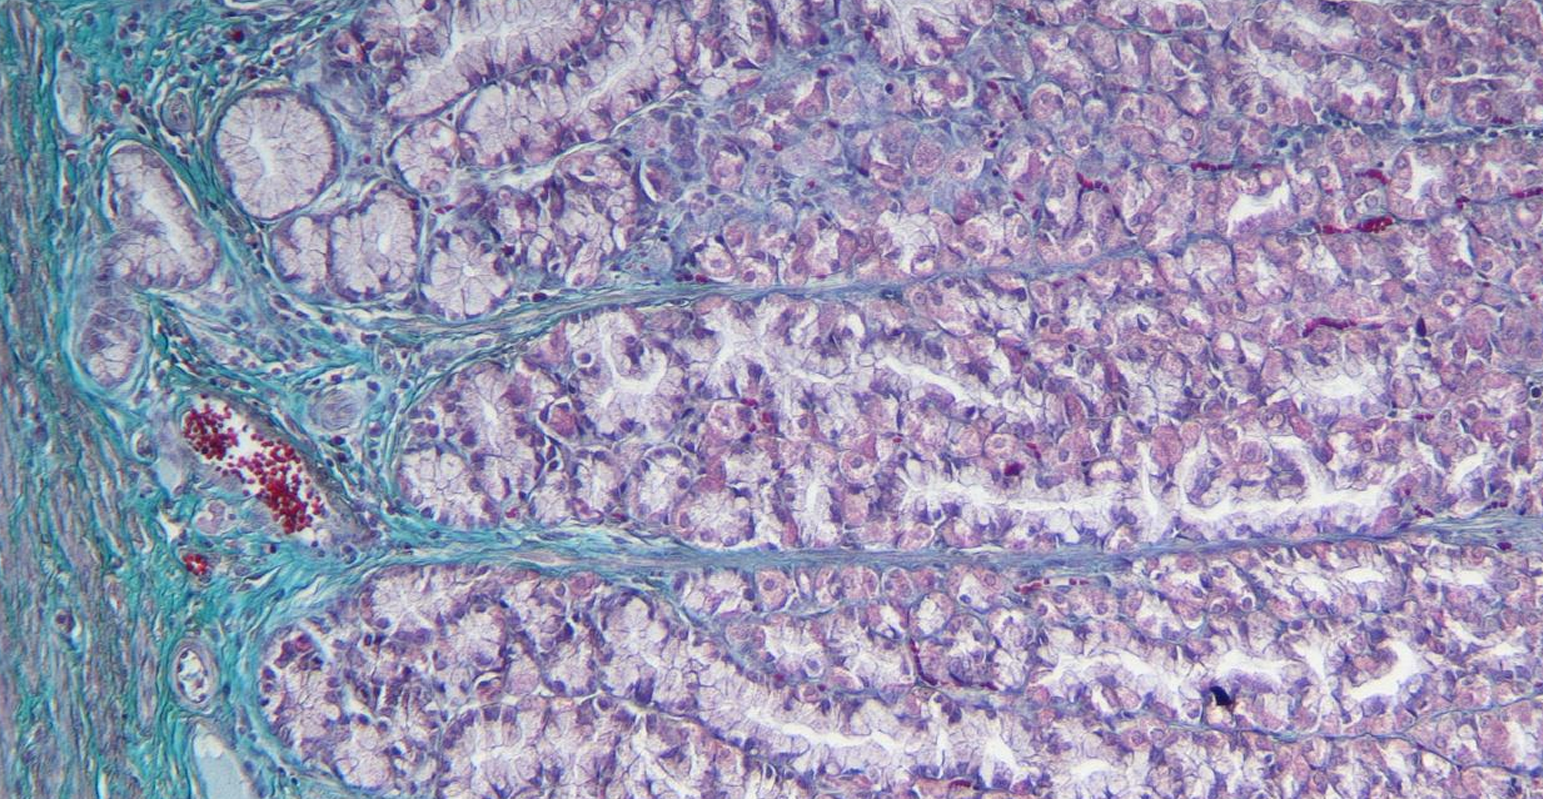

intestino grueso es la parte final del sistema digestivo, encargada de absorber agua y electrolitos, además de formar y eliminar las heces.

intestino grueso

colon